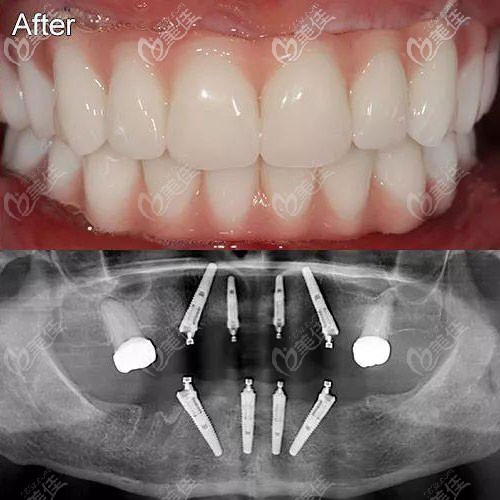

這有北京瑞泰口腔醫(yī)院豐臺分院的半口種植牙案例圖,大家可看下這種Allon4半口種植修復(fù)效果怎么樣~

(圖片中上面那張是戴上牙冠完成修復(fù)的效果,下面這張是4顆種植體在牙槽骨中的全景片)

4顆種植體是斜形植入,這樣的力學(xué)設(shè)計可以使半口種植牙受力呈現(xiàn)“拱形”特征,咬合力會均勻分散在牙床中,便于行使咀嚼功能。